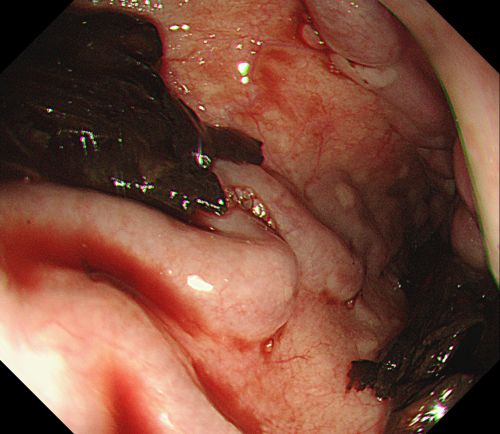

内镜下可见重度食管静脉曲张,且有较多血凝块。

内镜下胃底可见大量血液及血凝块。

患者旋即被推入手术室,麻醉三科刘际童主任为其进行气管插管、全麻,保持呼吸道通畅,并进行中心静脉置管等维持血压平稳。综合内科彭娅主任进行胃镜治疗,发现患者重度食管静脉曲张,胃底可见大量血液及血凝块;小心翼翼抽吸血液及清洗血块后,寻找到“犯罪血管”,在内镜下进行食管静脉曲张套扎+硬化剂注射治疗,封闭出血血管。